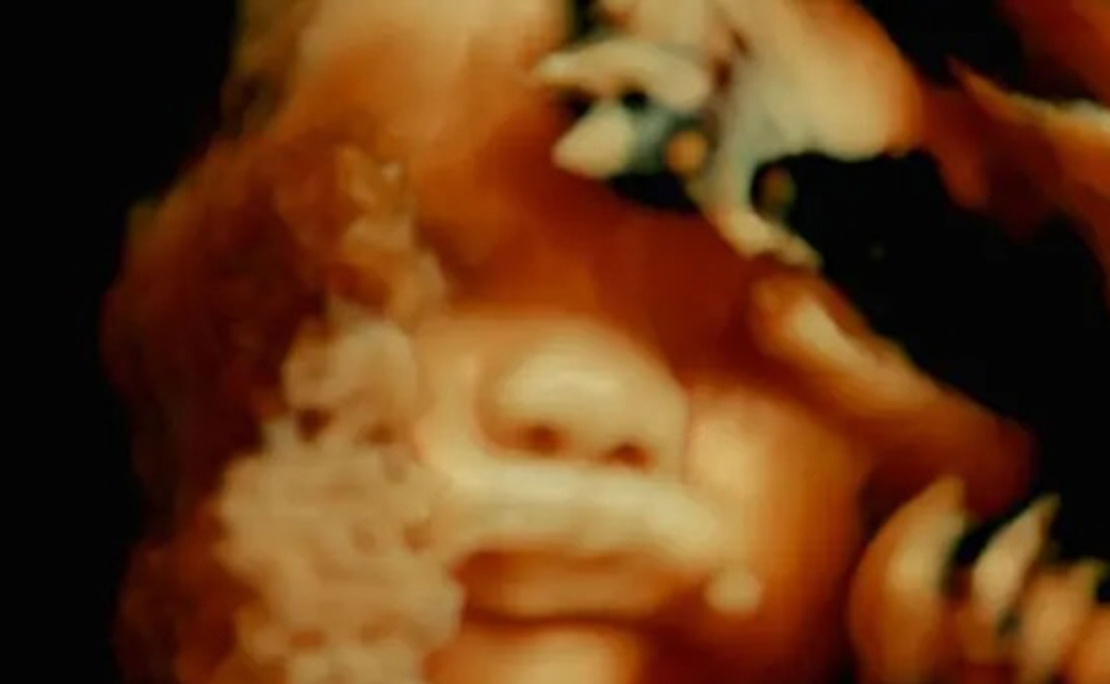

Vor fünf Jahrhunderten öffnete der Anatom Andreas Vesalius zum ersten Mal den Körper für den Blick der Wissenschaft. Sein Buch mit 250 detailreichen Holzschnitten der menschlichen Anatomie ist ein absoluter Meilenstein der Medizingeschichte. Dieser Film öffnet heute den Körper für das Kino. Man entdeckt, dass das menschliche Fleisch eine unerhörte Landschaft ist, die nur dank der Blicke und der Aufmerksamkeit der anderen existiert. Krankenhäuser, Orte der Pflege und des Leidens, sind Laboratorien, die alle Körper der Welt miteinander verbinden.  - Verleih -